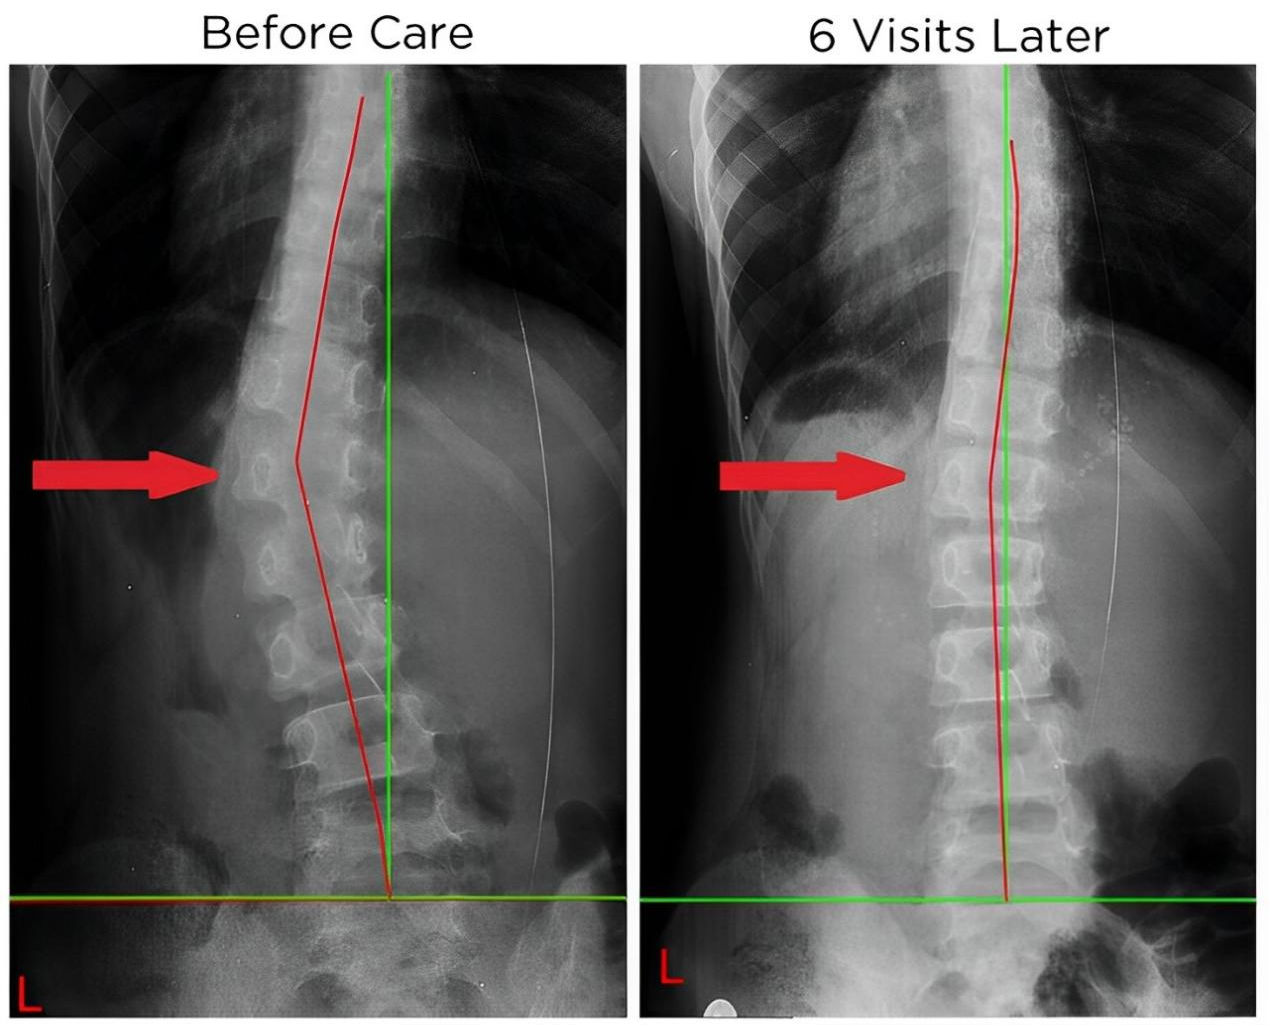

四、 恢復脊椎自然曲度

脊椎整復床的獨特設計能夠幫助恢復脊椎的自然曲度,改善脊椎側彎和不良姿勢,讓您重獲健康體態。

五、矯正完和矯正后的對比案例: